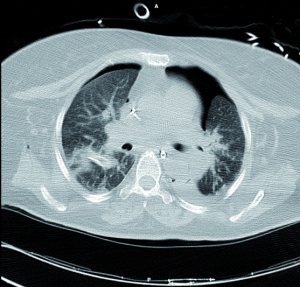

Führende Symptome sind: Dyspnoe, Hypoxie und Hyperkapnie – passend zu dem Schädigungssetting – und charakteristische Veränderungen in der Bildgebung (Röntgenaufnahme des Thorax und CT, siehe Abbildung 2). Historisch wird die Entwicklung einer klinischen Apparenz innerhalb von 24 bis 72 h beschrieben [10], jedoch konnte Pizov [14] bei der Mehrzahl seiner Patienten bereits unmittelbar nach dem Trauma eine klinische Symptomatik beschreiben. Eigene Erfahrungen zeigen, dass ein Beobachtungszeitraum von bis zu 48 h, bei entsprechender Traumagenese, bis zum Auftreten erster charakteristischer Symptome erforderlich sein kann. Als Prädilektionsstellen werden von Horrocks [7] die medialen, costophrenischen und subpleuralen Lungenanteile beschrieben.

Abbildungen 2 und 4: BwZKrhs Koblenz